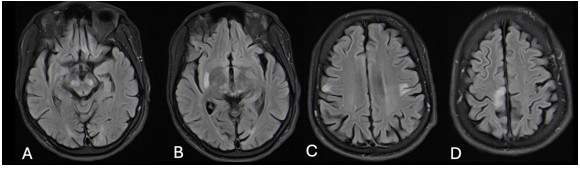

A 28-year-old male presented to the neurology unit at Inkosi Albert Luthuli Central Hospital with a ten-year history of progressively worsening bilateral tonic-clonic seizures, facial twitching, upper limb jerks and cognitive decline. He had a normal birth history and developmental milestones. He had been well prior to age 18, with no previous history of a hypoxic event or trauma. There was no family history of note. On social history, he had previously worked as a taxi driver and was a cigarette smoker with a 14 pack-year history. He drank alcohol on social occasions but did not have a history of illicit drug use. Despite being commenced on adequate doses of sodium valproate and carbamazepine by his district hospital, there was no improvement in seizure frequency. On examination he was noted to have mild cognitive impairment and a scanning dysarthria. Continuous focal movements of the right orbicularis oris and left orbicularis oculi were seen. He was observed to have stimulus-sensitive and action myoclonus of the right upper limb, as well as negative myoclonus. He was quadrispastic and had bilateral cerebellar dysfunction. His fundus examination was normal (with no cherry-red spot seen). Whilst in the ward, he was observed to have behavioural problems, having verbal and at times, physical, altercations with other patients in the neurology ward. In summary, this was a 28-year male patient who presented with features of a progressive myoclonic epilepsy (PME). On investigation his serological markers revealed normal urea and electrolytes, liver function and full blood count. Anti-nuclear factor and autoimmune encephalitis panel were negative. Metabolic screen including thyroid function, vitamin B12 (340 pmol/L) and lipid profile were normal. His serum lactate was normal (1.5 mmol/L). Sodium valproate and carbamazepine levels were within therapeutic range. Inflammatory markers were normal, while an infective screen including HIV, syphilis, herpes simplex virus and hepatitis were negative. Lumbar puncture revealed normal chemistry and was negative for herpes simplex virus, varicella-zoster virus, GeneXpert, syphilis and cryptococcus. His EEG revealed a slow background but no epileptiform activity. MRI brain showed multiple focal hyperintensities in the cortex as well as the thalami, midbrain and putamina (Figure 1). With no clear aetiology established, an axillary skin biopsy was performed. Histology revealed pathognomonic Lafora bodies in the sweat gland luminal cell layer. These are illustrated in Figure 2 as violet inclusion bodies after periodic acid Schiff (PAS+) staining.

Figure 1: Note multiple focal hyperintensities in the midbrain (A), thalami (B), putamina (B) and cortical regions (C, D).